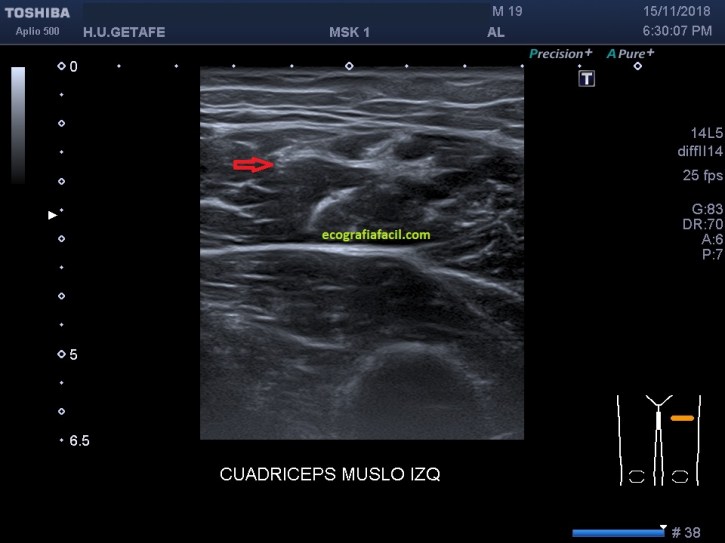

Paciente varón de 19 años, practica fútbol habitualmente, desde hace meses (no sabe precisar) y después de haber sufrido una lesión durante un partido al golpear el balón nota deformidad en la cara anterior del muslo izquierdo en el tercio proximal y dolor mientras hace ejercicio físico.

Empiezo la ecografía y compruebo una hendidura en la región afectada descrita anteriormente por el paciente. El lado contralateral parece normal. El Recto anterior izquierdo muestra en la zona «hundida» una imagen hiperecogénica y heterogénea en el teórico lugar del Rafe (flechas rojas), que en la porción más distal de la imagen heterogénea e hiperecogénica anteriormente descrita, es normal.

Imagen 2 , normal, imagen 1 y 3, patológico.

A 19-year-old male patient regularly practices football for months (he does not know how to specify) and after having suffered an injury during a match when hitting the ball, he feels deformity on the front of the left thigh in the proximal third and pain while exercising physical.

I start the ultrasound and check a cleft in the affected region described above. The contralateral side seems normal. The left anterior rectum shows in the «sunken» zone a hyperechogenic and heterogeneous image in the theoretical place of the Rafe, which in the most distal portion of the heterogeneous and hyperechogenic image described above, is normal.

Image 2, normal, image 1 and 3, pathological.